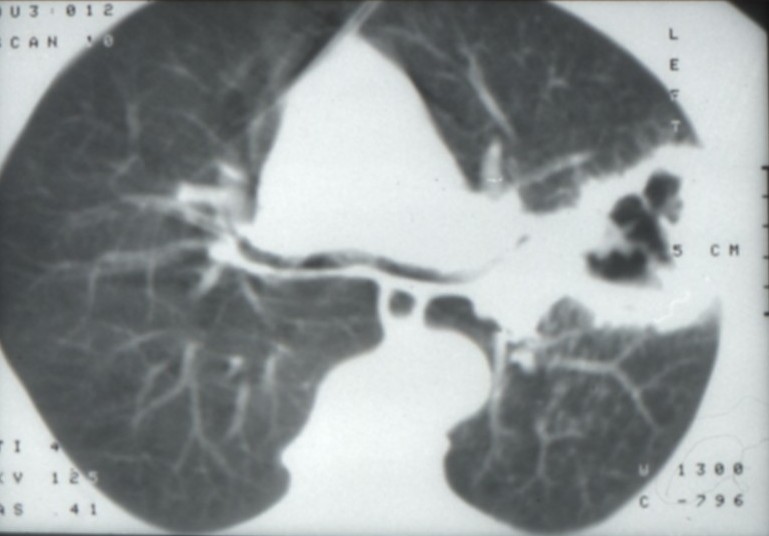

Cancers bronchiques